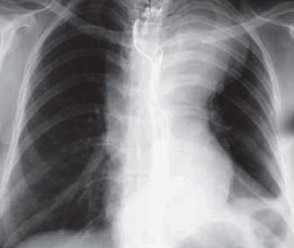

- Рентген - часто оказывается малоинформативным способом исследования. Можно лишь увидеть выраженную деформацию или аневризму.

- Рентгенография. В план рентгенологического обследования пациентов с аневризмой грудной или брюшной аорты включается рентгеноскопия и рентгенография грудной клетки, обзорная рентгенография брюшной полости, рентгенография пищевода и желудка.На заключительном этапе обследования выполняют аортографию, по данным которой уточняются локализация, размеры, протяженность аневризмы аорты и ее отношение к соседним анатомическим структурам.

- Рентгенодиагностика. Полипозиционная рентгенография грудной клетки выявляет тень расширенной дуги аорты и расширение сосудистого пучка. Часто определяется кальциноз стенок аневризмы. Рентгенография пищевода и желудка позволяет обнаружить смещение пищевода и кардии желудка. Инвазивная рентгеноконтрастная аортография применяется, главным образом, для оценки кровотока в ветвях аорты.